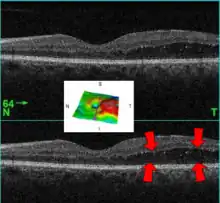

| A 61-year-old man with medical history of type 2 diabetes that presents a macular edema, evidenced by an OCT (the edema marked with arrows). The central image is a 3D reconstruction of the retinal thickness (the edema is coloured in red). | |